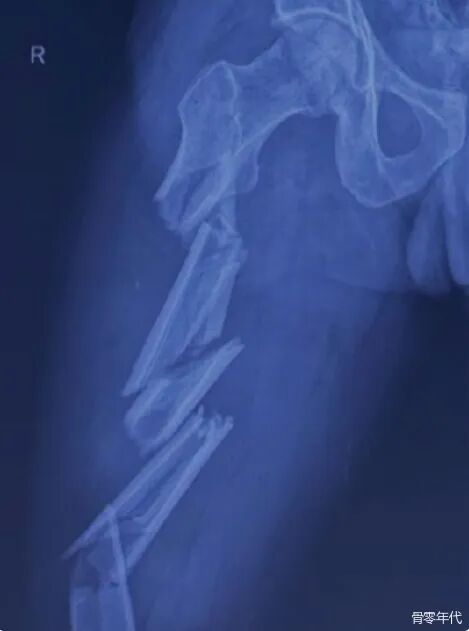

影像学表现